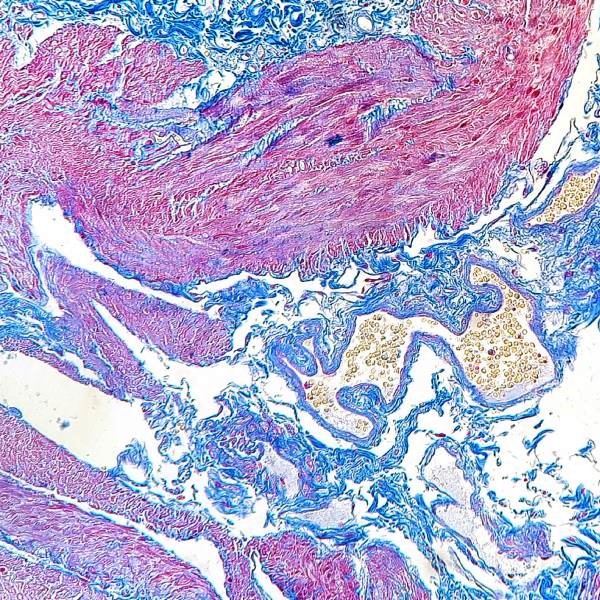

El kit de tricromía Azan es una modificación del kit Mallory Trichrome para la tinción del tejido conectivo. Se utiliza para visualizar los músculos, las fibras de colágeno, las células gliales, las células glomerulares, las cromatinas y los eritrocitos de una misma sección. El kit contiene dos colorantes ácidos: Azocarmina G y contratinción de Azul de Anilina. La Azocarmina G se utiliza en la fase inicial del procedimiento de tinción, y el Azul de Anilina se utiliza en la fase final, después de tratar la sección con ácido fosfomolíbdico. Para obtener resultados de tinción de alta calidad, es necesario teñir la sección con Azocarmina G, y luego diferenciarla progresivamente con solución alcohólica de anilina para permitir la contratinción de ciertas estructuras(como el colágeno) de la sección.

Núcleos, eritrocitos, gránulos acidófilos de la hipófisis - rojo

Neurofibrillas (neuroglía) - tonos de rojo

Fibras musculares - de color rosa a rojo-rosado

Colágeno, reticulina, membranas celulares basófilas, estroma glomerular renal, membranas basales - azul a azul oscuro

Fibras elásticas -sin color